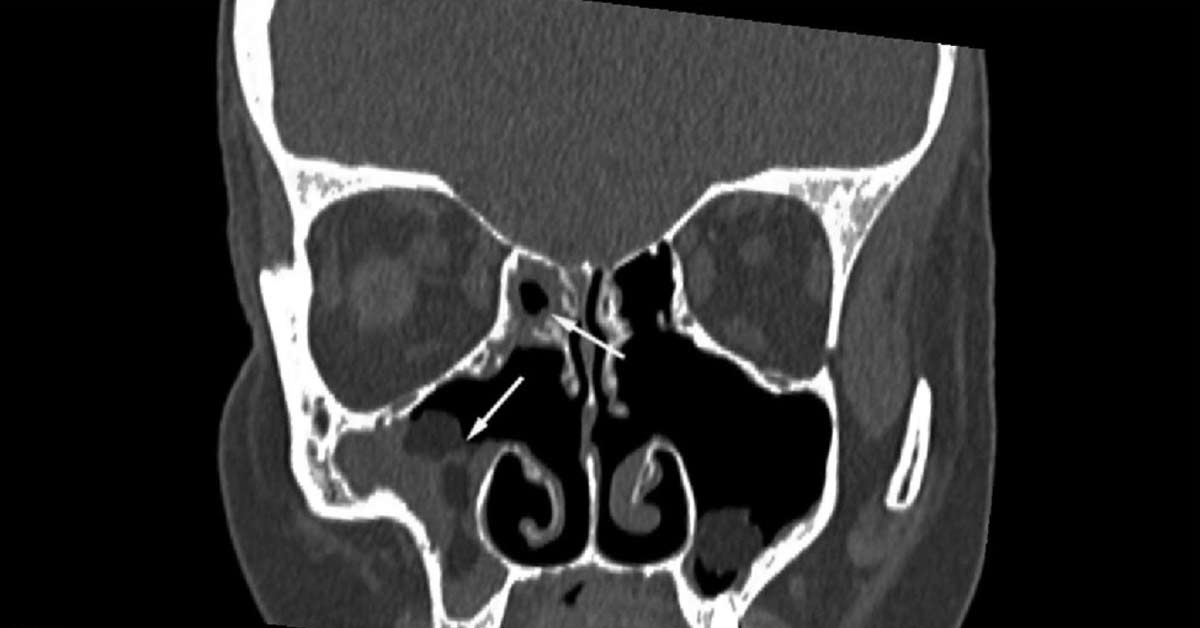

O esfenoide é um osso que fica bem lá no fundo da sua cabeça, atrás do nariz e dos olhos. Quando ele inflama, a sinusite esfenoidal pode causar sintomas que parecem dor de cabeça comum, mas com uma intensidade maior e, muitas vezes, acompanhada de secreção que desce pela garganta. O diagnóstico preciso é fundamental. O otorrino poderá solicitar exames, como uma tomografia, se necessário, para visualizar a área afetada e confirmar a inflamação. Não se assuste, o objetivo é justamente chegar a um tratamento eficaz.

Existe algum exame específico para diagnosticar sinusite esfenoidal?

O diagnóstico geralmente envolve um exame físico e histórico médico. Exames de imagem como tomografia computadorizada são fundamentais para visualizar o seio esfenoidal. Eles ajudam a identificar a inflamação e possíveis obstruções.